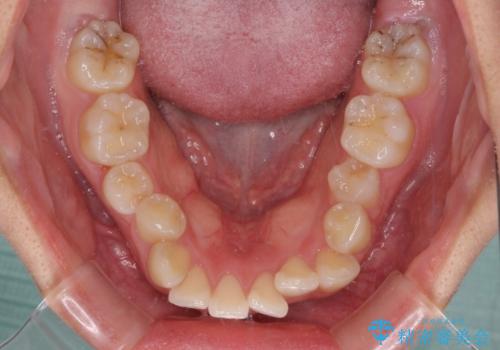

上下ともに歯列が前方に突出していたため、上下左右の第一小臼歯4本を抜去する方針(既に上顎は抜歯されています)で、ワイヤー装置による矯正治療を行うこととしました。

舌の突出癖による影響もあったため、舌のトレーニングを並行して実施しました。

舌の突出癖があり、咬合力も強かったため、治療期間は長くなることが懸念されましたが、舌のトレーニングをしっかりと行っていただいたこともあり、2年弱で治療を終えることができました。